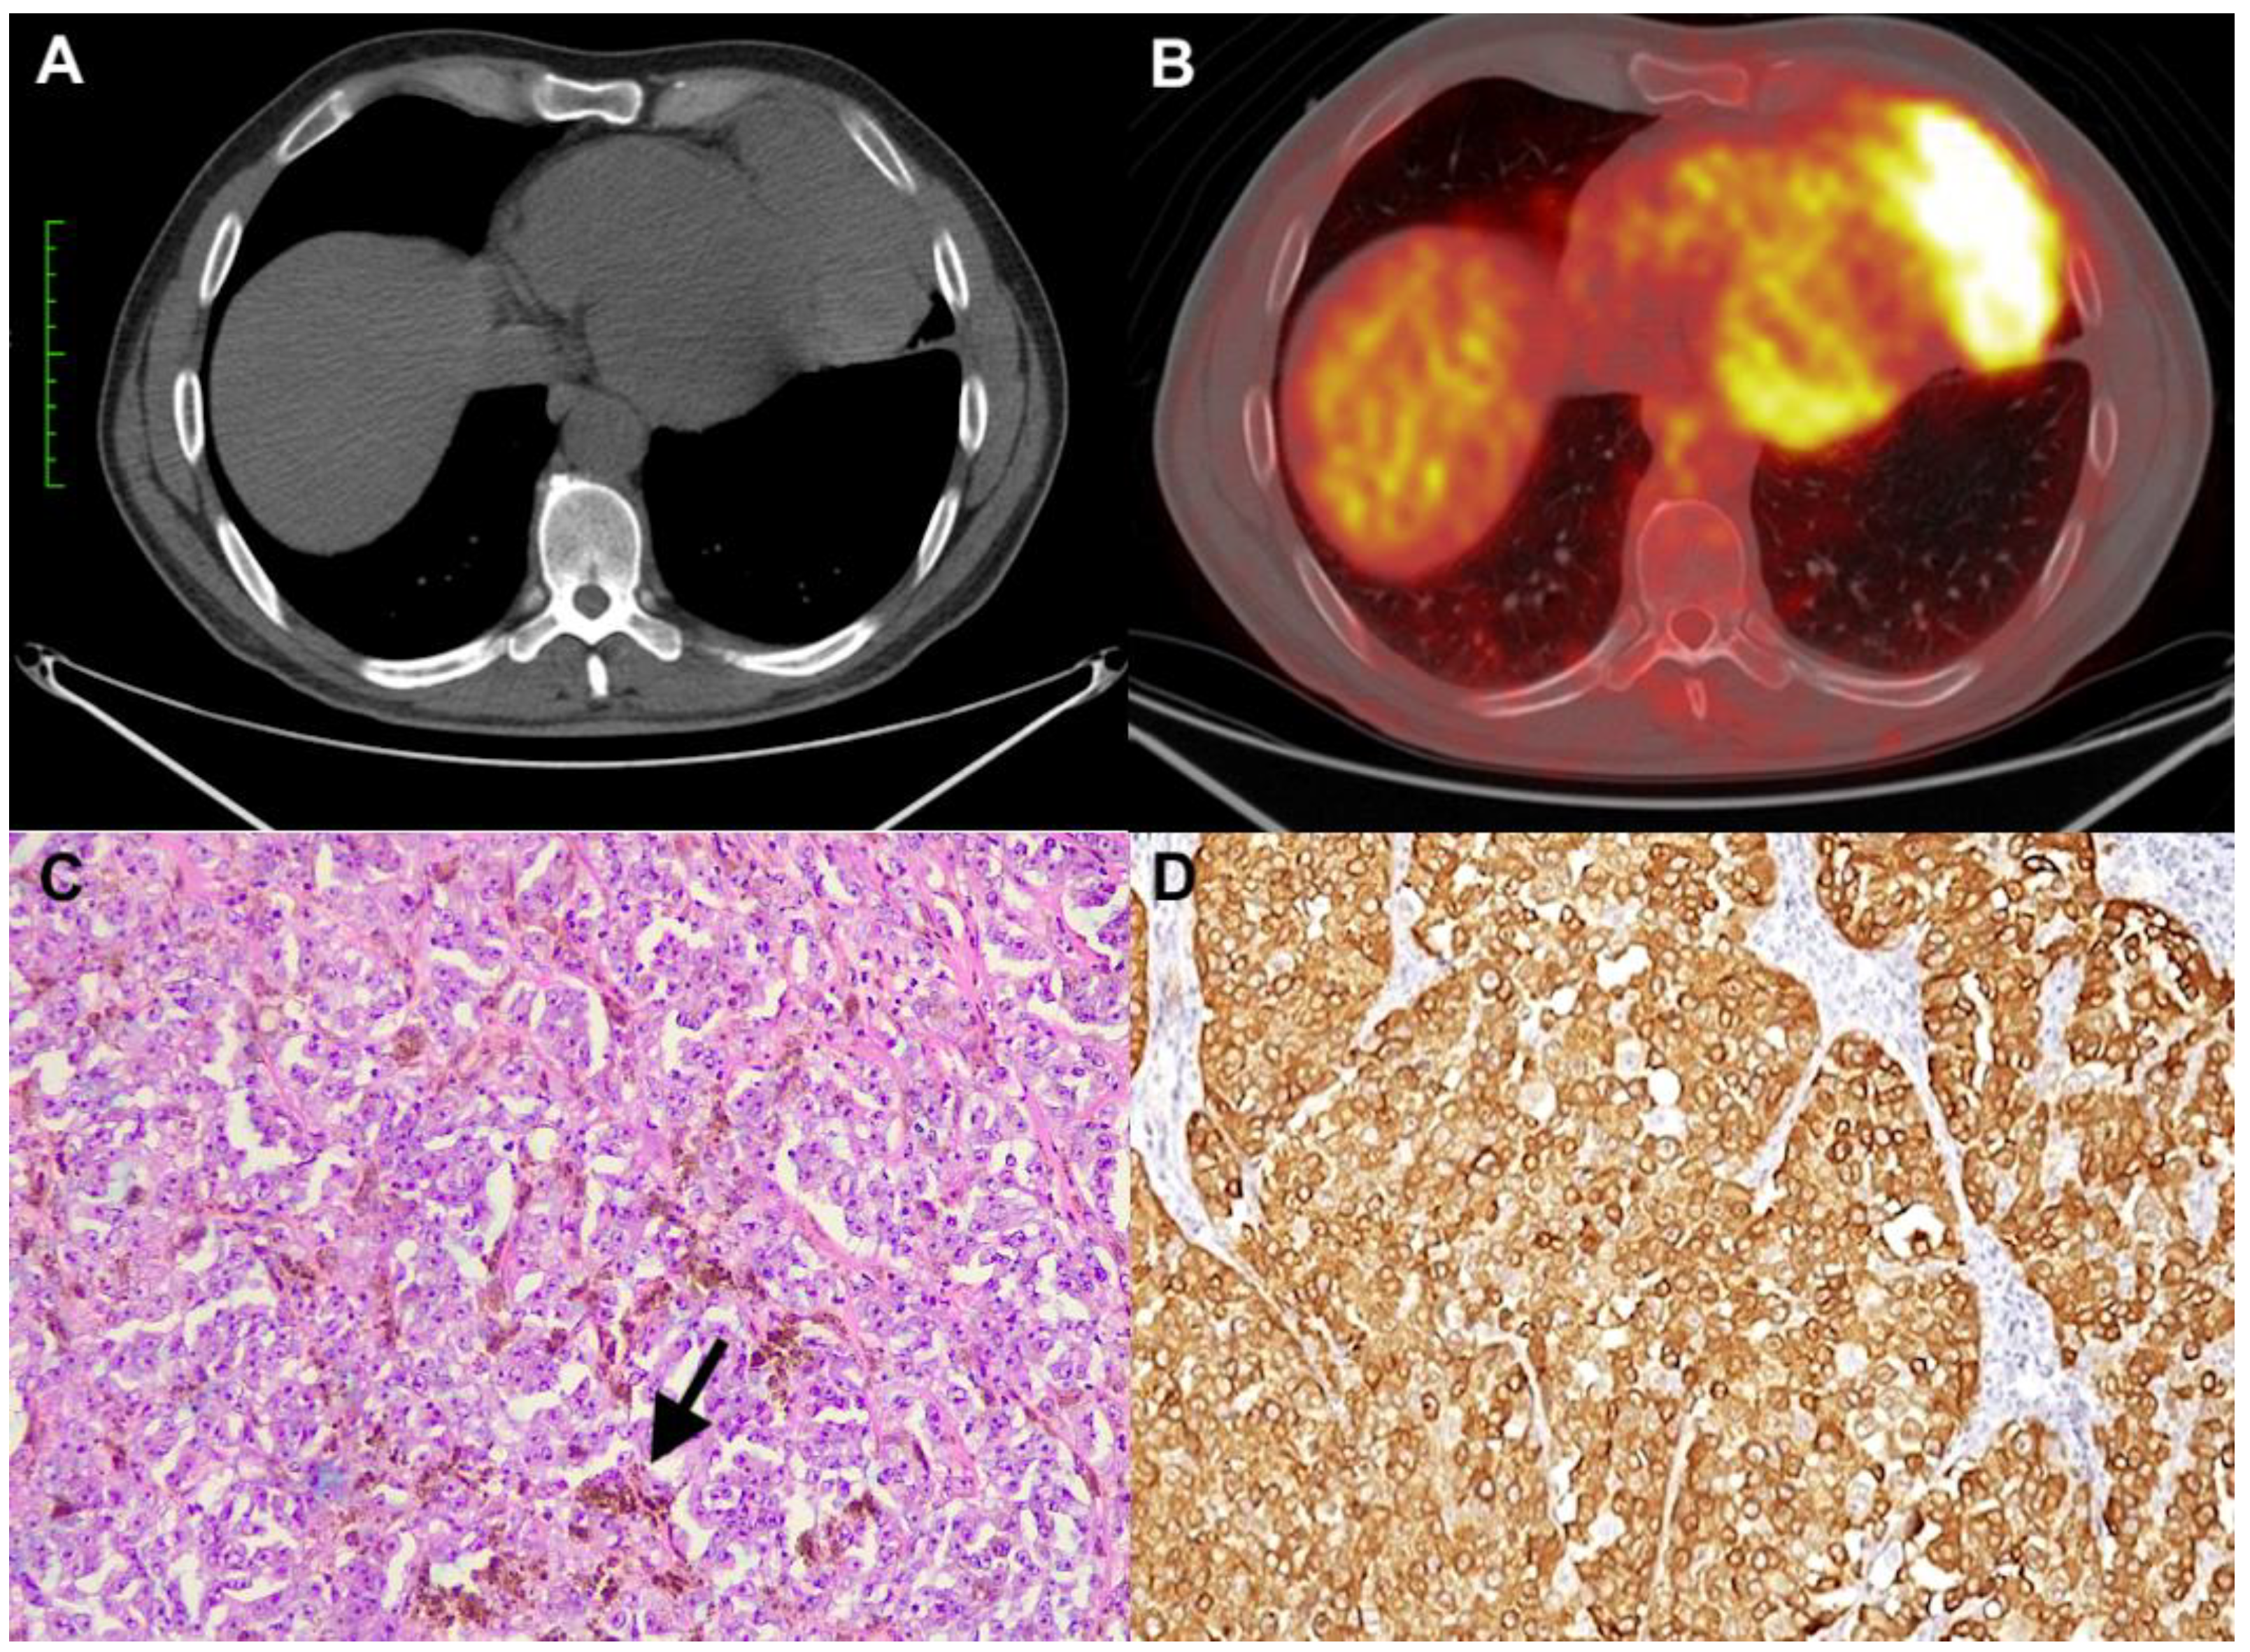

A 53-year-old man with an unremarkable past medical history presented to the local emergency room complaining of breathlessness. The chest X-ray showed gross widening of the mediastinum with a well-defined homogenous radio-opaque shadow. A contrast-enhanced chest computerized tomography (CT) scan demonstrated a mediastinal mass with a size of 10.5 cm × 4 cm, strictly adherent to the diaphragm and pericardium (Figure 1A). The diagnostic work-up was concluded with a positron emission tomography (PET) scan that showed pathological uptake only in the mass with a standard uptake volume (SUVmax) of 20.8 (Figure 1B). Because this finding was suggestive of a primary neoplastic process of the anterior mediastinum, likely a thymoma, surgery was planned. Through a left mini-thoracotomy approach, thymectomy en bloc with partial pericardium resection and an atypical resection of the left lower lobe were performed. The procedure was uneventful, and the patient was discharged on the fifth postoperative day. The gross specimen revealed a solid encapsulated mass with a maximum diameter of 10 cm, which was brownish at the cut surface. Histologically, the tumor was composed of atypical epithelioid cells, with large eosinophilic cytoplasm, prominent nucleoli, and a solid growth pattern. Abundant melanic pigment was also present (Figure 1C). There were thymic remnants at the periphery of the tumor. The immunophenotypic panel showed strong positivity for melanocytic differentiation markers: S100, Melan A/MART1 (Figure 1D), HMB45, and SOX10. Immunoreactions for cytokeratin, CD5, CD117, p40, PAX8, and neuroendocrine markers were negative. No mutations of BRAF were detected by the real-time PCR method and EWSR rearrangement by fluorescence in situ hybridization (FISH). An attempt was made to carry out more in-depth molecular characterization using next-generation sequencing methodology, but the characteristics of the sample (extensive necrotic phenomena) did not allow for adequate DNA quality for analysis. The final diagnosis of malignant melanoma was made. No primary cutaneous and non-cutaneous melanomas were detected upon dermatological, ophthalmological, and gastroenterological examination. After six months, a polypoid endoluminal mass of 4 cm in the distal ileum was identified during radiological follow-up. Surgical resection was performed. The final pathological examination was conclusive for malignant melanoma. Following a multidisciplinary discussion, considering the radicality of the surgical interventions, it was decided not to perform adjuvant treatment, and the patient is under follow-up. Currently, the patient is still alive and free of disease seven years after the first surgery.

Figure 1. CT scan showing a voluminous mass of the anterior and inferior mediastinum (A) with high pathological uptake (SUVmax: 20.8) (B). Histologically, the tumor was composed of large and nucleolated cells with deposition of melanic pigment (arrow) (C) (hematoxylin and eosin stain, original magnification ×100)). The neoplastic cells were strongly positive for Melan A (D) (immunohistochemistry, original magnification ×200)).